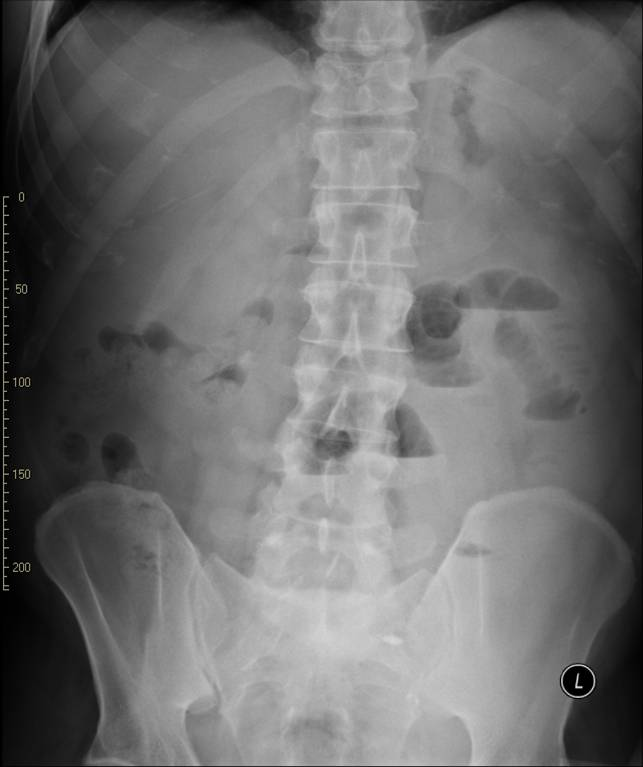

• Plain abdominal radiographs are usually sufficient to raise suspicion for bowel obstruction. In most cases, the radiologic appearance is indicative of the level of the blockage (stomach, small or large bowel). Mechanical obstruction can be incomplete but also it can become complete as the passage function wears off in the strain. Clinical data and patient history (previous abdominal surgery, medication, cancerous state etc.) are all important details in order to help to differentiate the types of obstruction from one another.

21. Right image: plain abdominal X-ray showing distended bowel loops, with wide air-fluid levels. Left image: plain abdominal radiograph showing distended colon until the sigmoid segment, with wide air-fluid levels. The obstruction is most likely to be at the level of the sigmoid or the rectum.